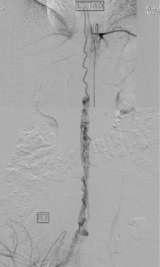

Spinal vascular malformation is a very rare condition. It is an abnormal tangle of blood vessels on, in, and/or near the spinal cord (Figure 1).

Intramedullary and pial AVMs are considered to be congenital conditions (Figure 1). Larger malformations tend to cause symptoms in a younger age group than smaller AVMs. In fact, smaller malformations can be completely silent. Symptoms from spinal AVMs can occur in a gradual fashion or acutely and dramatically. The symptoms include abnormal sensation in the body, back pain, weakness in the extremities, sexual dysfunction, and bowel/bladder disturbances.